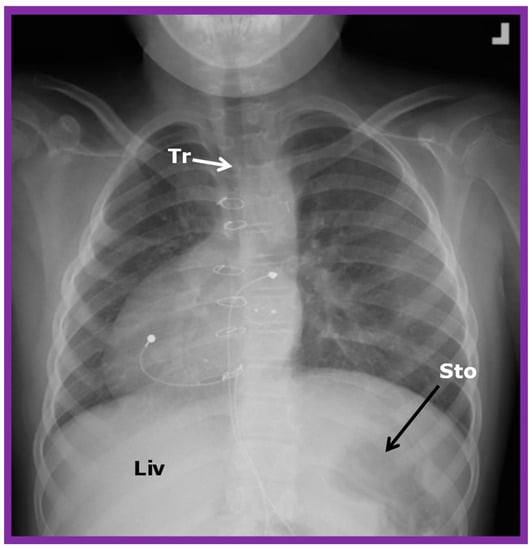

If the heart is positioned in the right chest (Figure 2 and Figure 3), it is described as dextrocardia. The term dextrocardia should be used for conditions in which the cardiac malposition is intrinsic or primary and is not due to displacement of the heart secondary to the thoracic cage or lung abnormalities [3].

Figure 3. Chest X-ray of a child demonstrating the heart in the right chest (dextrocardia). The positions of the liver (Liv) on the right side, and stomach (Sto) on the left side are seen, indicative of visceral situs solitus. This is described as isolated dextrocardia. Tr. Trachea; inverted L, indicates left. Sternal and pacemaker wires (not labeled) are seen and are related to prior surgery. Modified from reference [5].